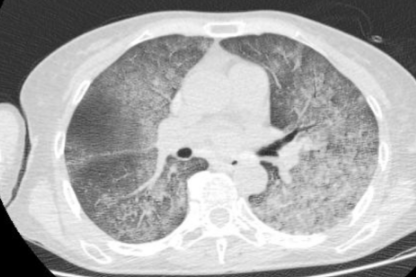

2024-7-4胸部CT影像

由于抗真菌治疗效果不佳,怀疑是否合并了其他病原菌感染。第二次支气管镜检查。检查发现,气管、隆突、左肺及右肺各级支气管管腔内仍有大量白色稀薄痰液涌出。支气管肺泡灌洗液二代测序报告显示近平滑念珠菌,于是加用了氟康唑进行抗真菌治疗。然而,经过一周积极治疗后,于2021年7月4日复查胸部CT显示,患者的双肺仍呈“大白肺”样改变,病变更为严重。